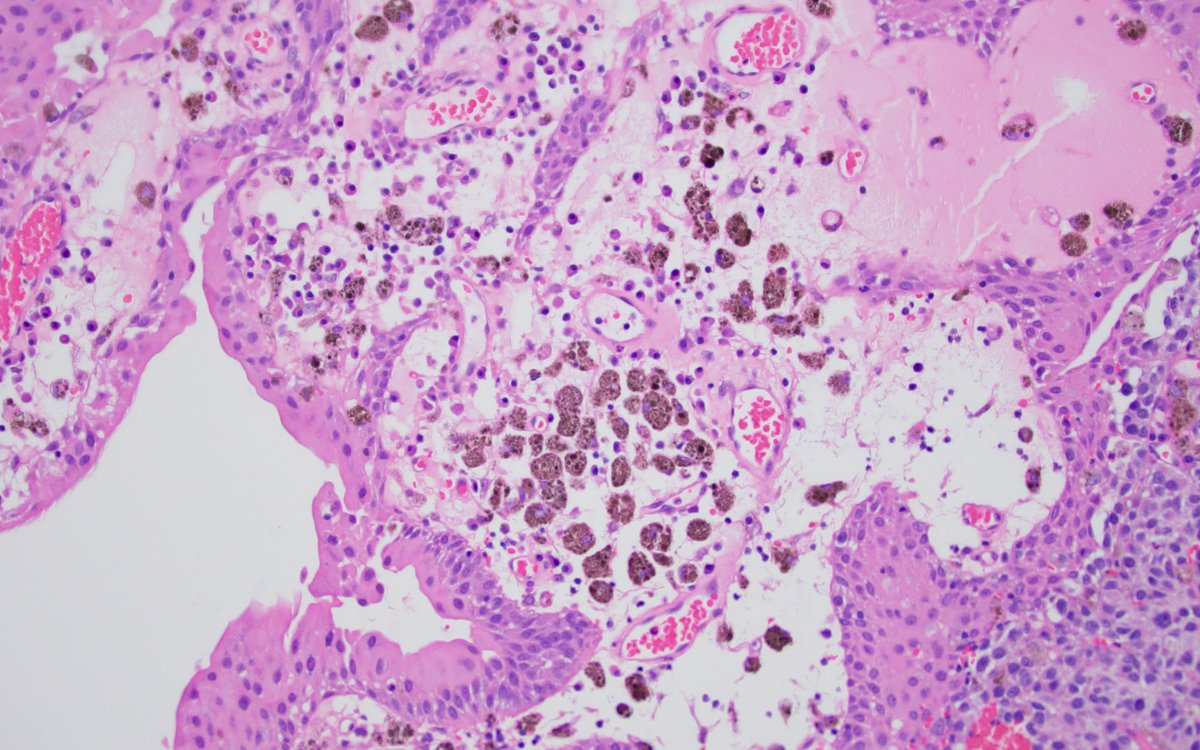

Lipid-rich urothelial carcinoma ✔️frequently associated with conventional urothelial carcinoma ✔️ lipid nature of the vacuolar content has been confirmed by EM ✔️ poor prognosis ✔️ + CK7, CK20 (photo), 34betaE12 #gupath #pathology #uropathology